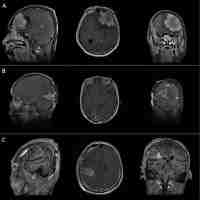

| Abstract | BackgroundThe progesterone receptor (PR) is variably expressed in most meningiomas and was found to have prognostic significance. However, the correlation with patient age, tumor location, time to recurrence, and pattern of regrowth has scarcely been discussed.MethodsA surgical series of 300 patients with meningiomas is reviewed. The PR expression was classified as: 0. absent; 1. low (<15%); 2. moderately low (16–50%); 3. moderately high (51–79%); 4. high (≥80%). The PR values were correlated with the patient age and sex, meningioma location, WHO grade, Ki-67 MIB1, recurrence rate, pattern of recurrence (local-peripheral versus multicentric diffuse), and time to recurrence.ResultsThe PR expression has shown lower rate of high expression in the elderly group (p = 0.032) and no sex difference (including premenopausal versus postmenopausal women), higher expression in medial skull base and spinal versus other locations (p = 0.0036), inverse correlation with WHO grade and Ki67-MIB1 (p < 0.0001). Meningiomas which recurred showed at initial surgery higher rates of low or moderately low PR expression than the non-recurrent ones (p = 0.0004), whereas the pattern of regrowth was not significant. Higher rates of PR values ≥80% were found in cases with time to recurrence >5 years (p = 0.036).ConclusionThe higher PR expression in medial skull base meningiomas, the significant correlation with the time to recurrence, the lack of difference of PR expression between premenopausal and po... |